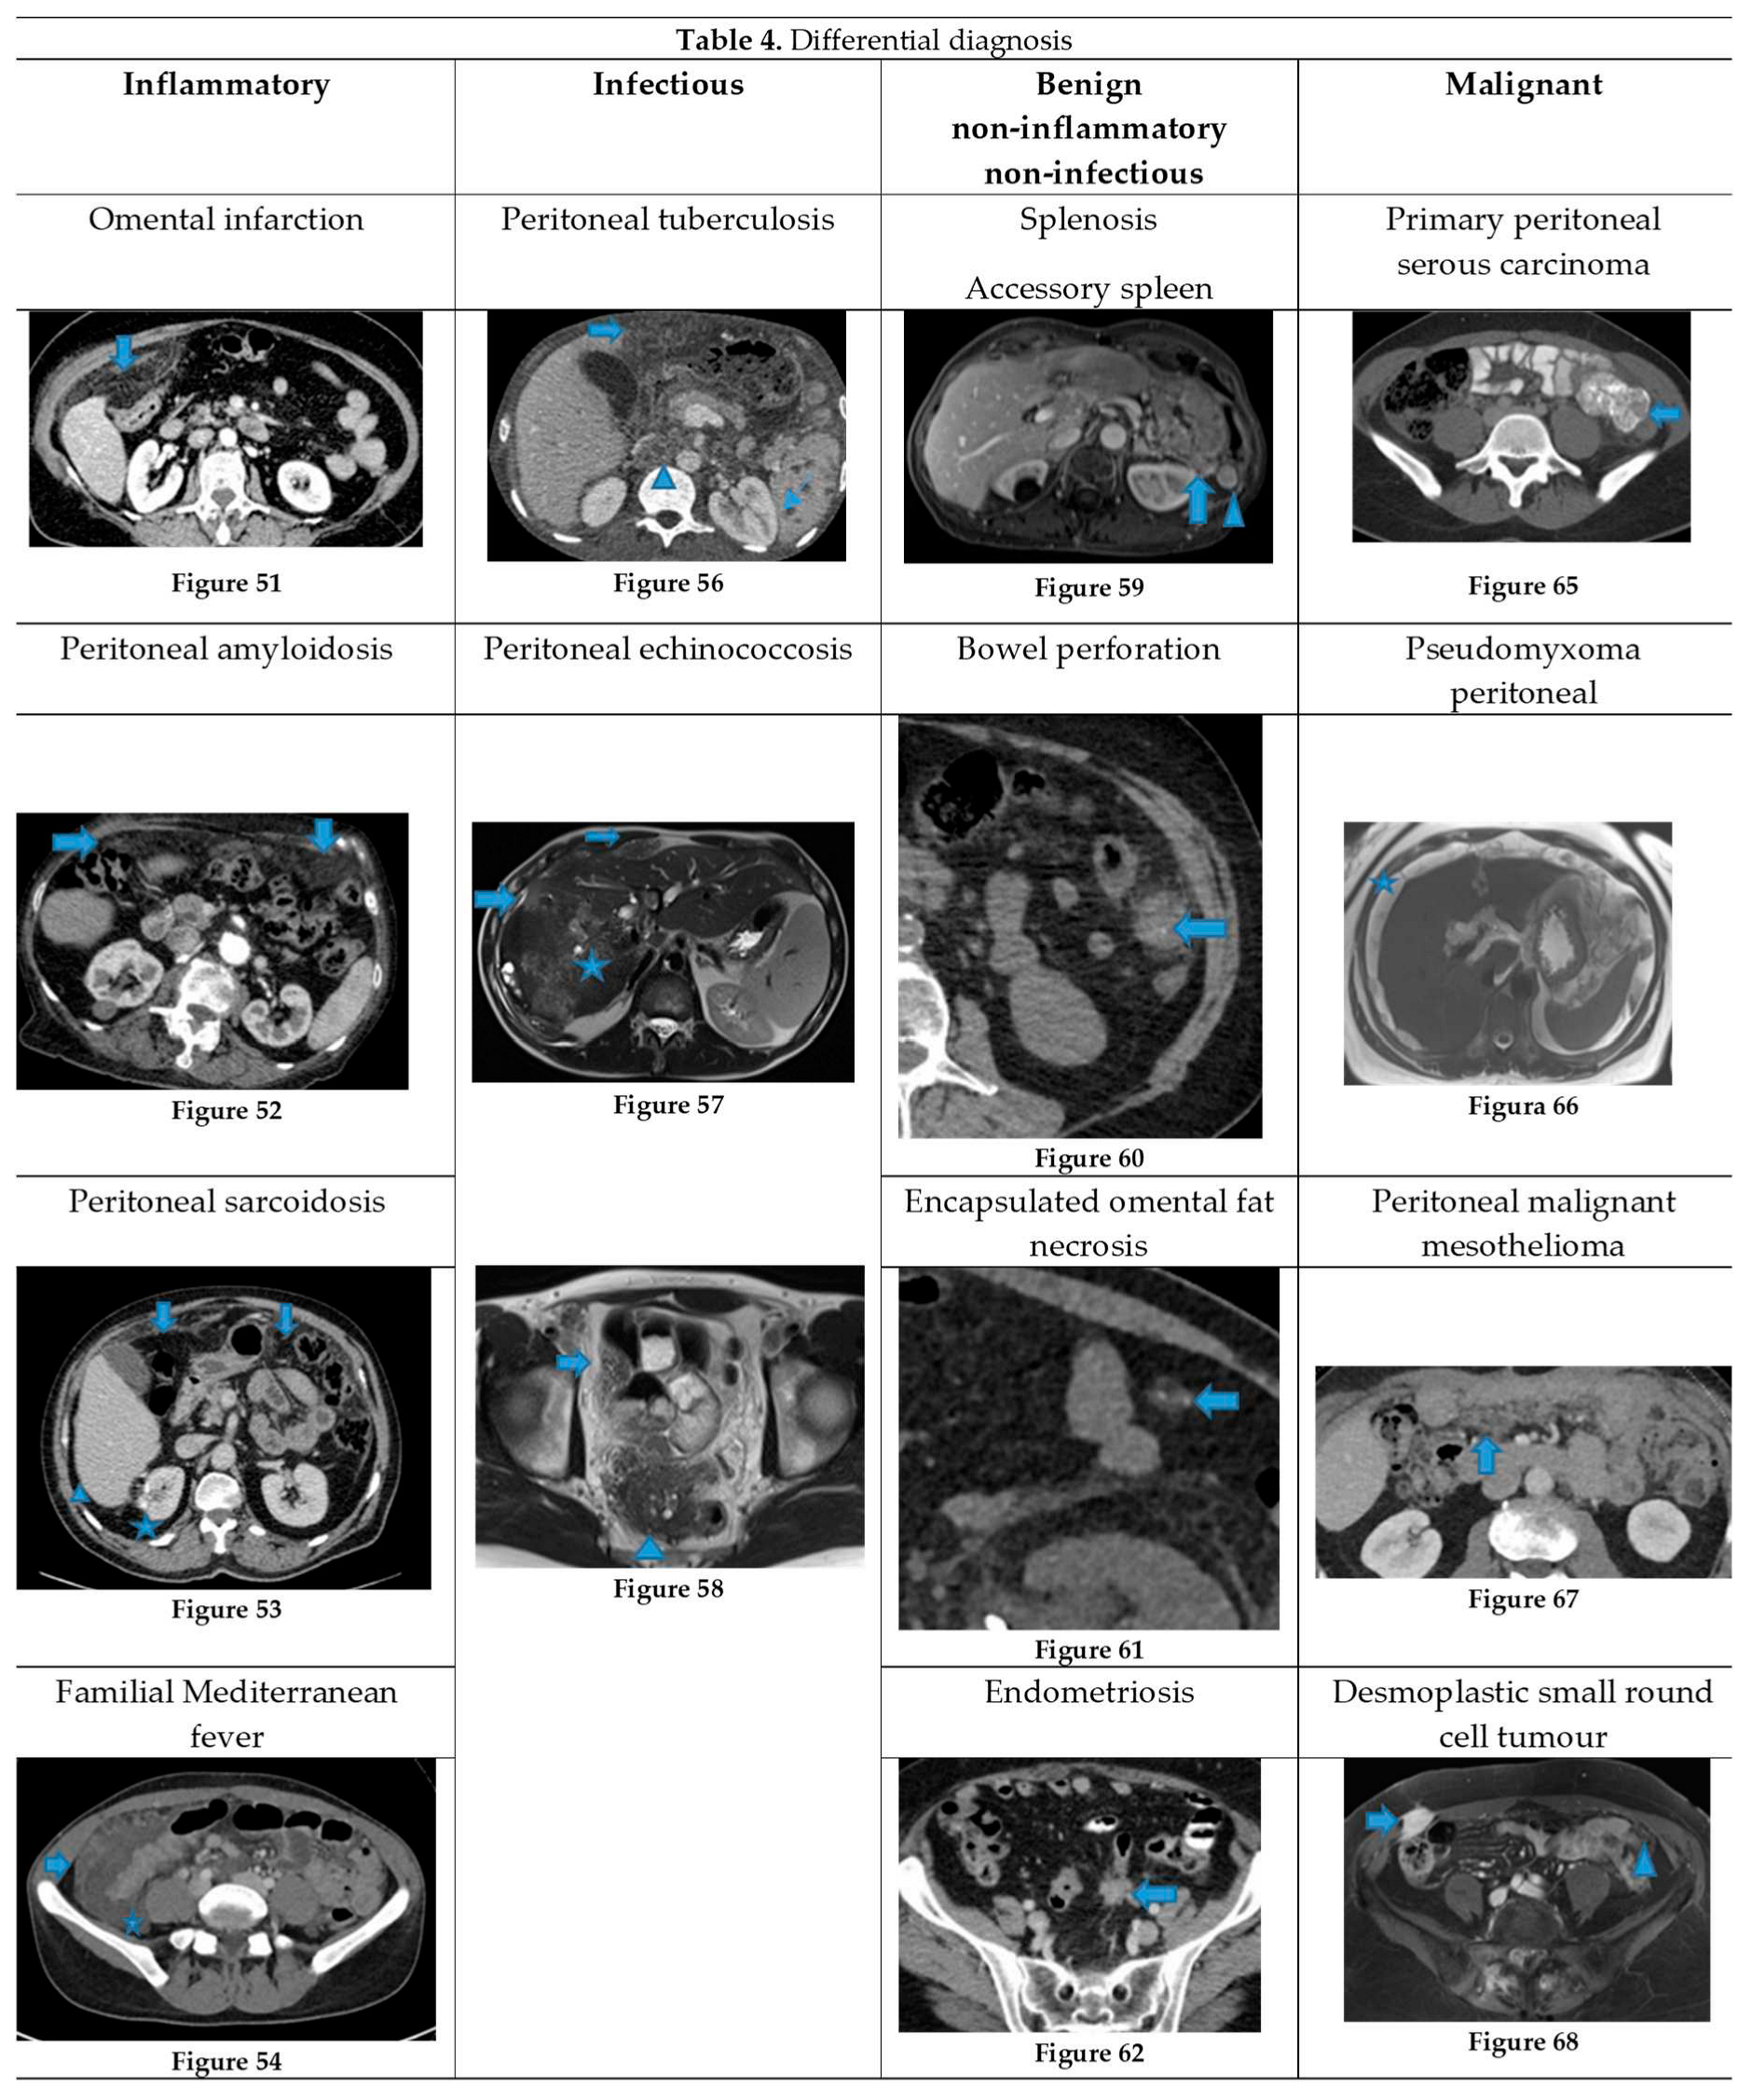

Figure 26.

Axial CE-CT (A). PC from stomach adenocarcinoma: Stellate mesentery. Axial CE portal phase FST1WI (B). PC from lobular breast adenocarcinoma: Stellate mesentery, notice the perivascular distribution. Axial CE-CT (C), axial T2WI (D). PC from stomach adenocarcinoma: Isolated perivascular deposit within the mesentery, as a soft tissue mass surrounding a branch of the SMV.